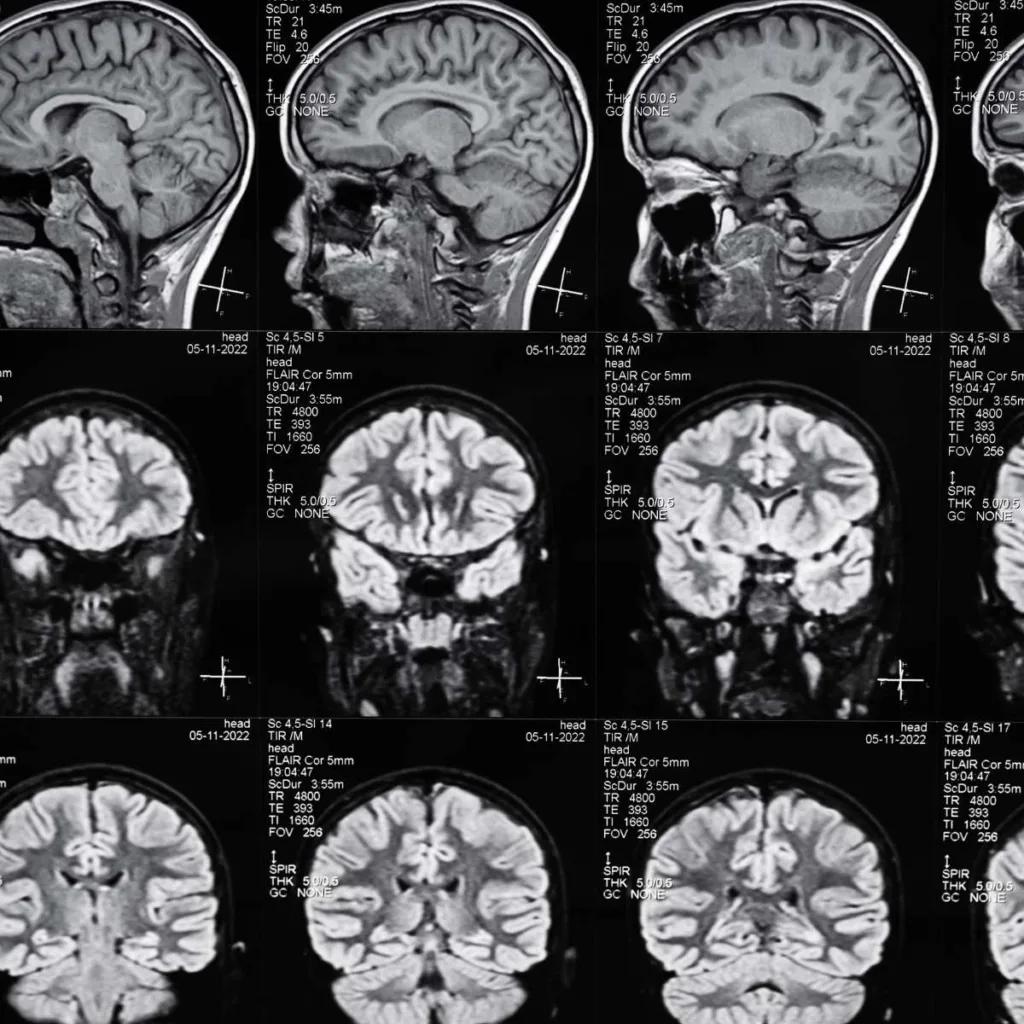

Resonancia Magnética de Cabeza